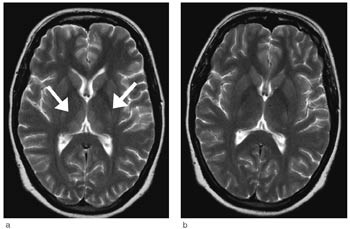

EEG viste uspesifikk langsom aktivitet over begge hemisfærer uten tegn på encefalitt. Cerebral CT viste normale forhold. Da pasientens bevissthetsnivå var redusert og fordi tilstanden var uavklart, ble det funnet indikasjon for MR-undersøkelse av cerebrum samme natt. Undersøkelsen viste bilaterale symmetriske lesjoner i mediale thalamus, corpora mammillaria, den periakveduktale gråe substans og i bunnen av 4. ventrikkel, forenlig med Wernickes encefalopati (fig 1).

MR-kontroll fire uker etter den første undersøkelsen viste tilbakegang av forandringene i hjernestammen og fortsatt bilateral lesjon i thalamus (fig 2).

Vi baserte diagnosen på den nevnte triaden konfusjon, øyemuskelpareser og ataksi samt karakteristiske MR-funn (10). Denne pasienten hadde symmetriske områder med forhøyet T2-signal i dorsomediale thalamus, periakveduktalt i mesencefalon, i hypothalamus og i corpora mammillaria, noe som er typisk for Wernickes encefalopati (10) – (12). Hos enkelte pasienter vil man se kontrastopptak i disse lesjonene, men dette er ikke obligat. Hos vår pasient ble det ikke gitt intravenøs kontrast. Diffusjonsvektede MR-bilder er en sensitiv metode for å påvise intracellulært ødem hvor diffusjonen er redusert. Ved hjerneinfarkter betyr redusert diffusjon som regel en irreversibel vevsskade, som utvikles til nekrose. Det er de siste årene kommet flere rapporter som viser at enkelte av pasientene med Wernickes encefalopati har redusert diffusjon i mediale thalamus (11, 12). I utgangspunktet vil et slikt MR-funn indikere en alvorligere prognose med større risiko for vevshenfall. Hos vår pasient ble det ikke påvist redusert diffusjon. Det er også typisk å se en tydelig tilbakegang av signalforandringene ved MR-undersøkelse etter få dagers behandling med tiamin (10). Hos vår pasient observerte vi dette. Ved den første kontrollundersøkelsen var det en begynnende normalisering, og etter 2 1/2 måneder var normaliseringen fullstendig.